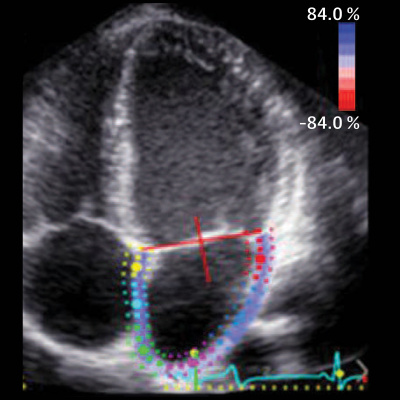

Electrocardiographic markers of atrial myopathy are associated with dementia, but it is unclear whether 2-dimensional echocardiographic––defined LA function and size are associated with dementia. JAMA Senior Editor Philip Greenland, MD, discusses study findings with Wendy Wang, MPH, and Lin Yee Chen, MD, authors of Association of Echocardiographic Measures of Left Atrial Function and Size With Incident Dementia